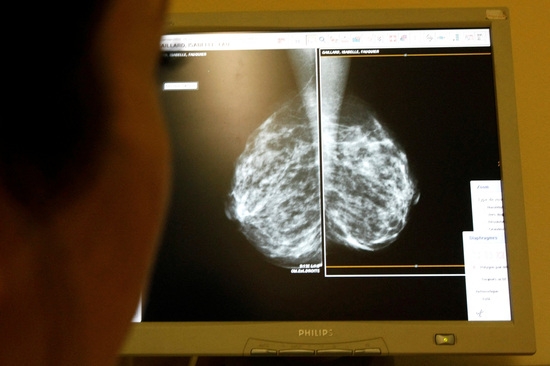

AI는 이미 다양한 분야에서 암 진단과 치료에 활용되고 있다. 프랑스 퀴리 연구소는 딥러닝 AI 도구를 개발해 원인을 알 수 없는 암을 진단하는 데 성공했으며, EU의 판카임 프로젝트는 췌장암 조기 발견 알고리즘을 개발했다. 또한, 스웨덴 연구진은 AI가 유방암 발견에 도움이 될 수 있음을 입증했다.